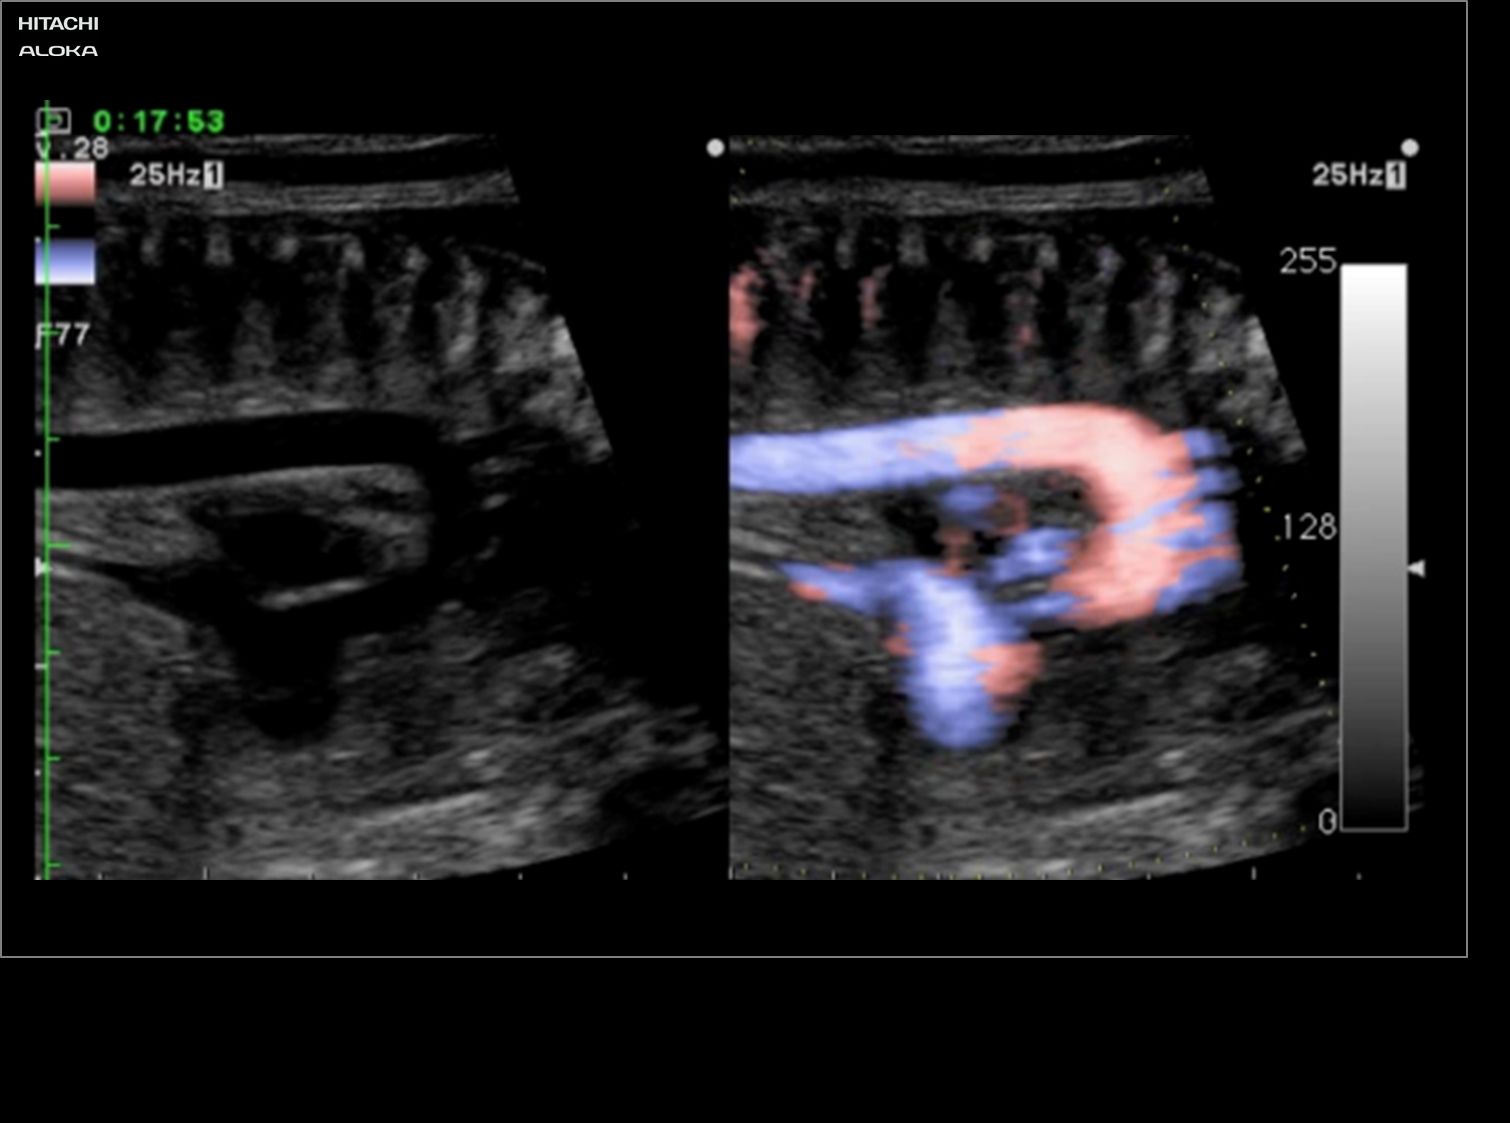

eFLOW는 폐정맥의 미세 혈관뿐만 아니라 대동맥 궁과 같은 큰 혈관을 나타냅니다. 최소한의 피와 인상적인 이미지 품질로 태아의 심장에서 가장 작은 해부학 적 세부 사항을 명확하게 표시하는 데 도움이됩니다.